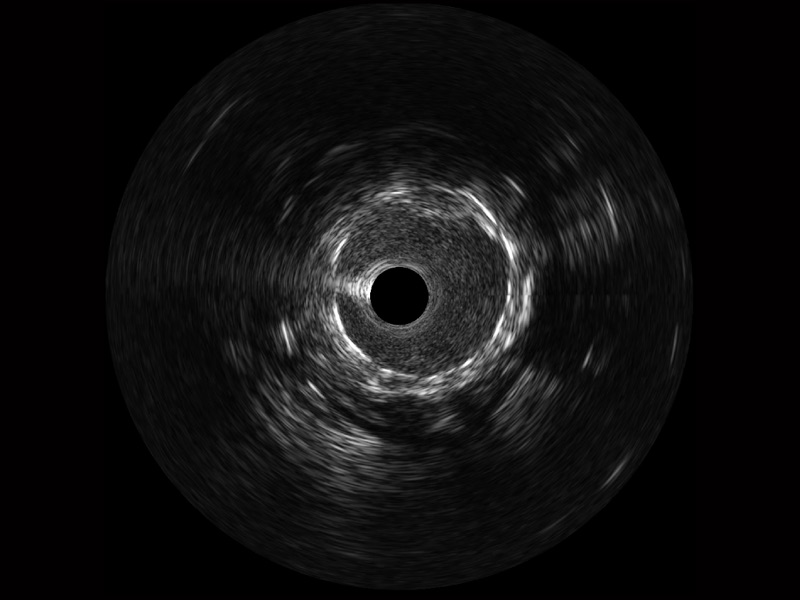

云顶集团官网宽频IVUS图像

对比传统IVUS导管成像,云顶集团官网宽频IVUS图像的近场支架梁显影更细腻,远场中膜外血管仍清晰可辨,兼顾远中近,兼顾分辨力与穿透深度